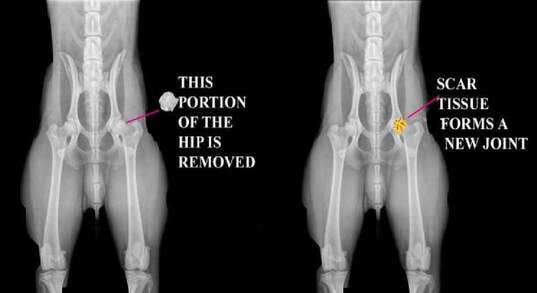

FHO 是將股骨頭及部分股骨頸切除,使得骨頭與骨盆之間形成類似纖維化假關節(pseudoarthrosis),藉此減少疼痛並恢復活動。如同醫療文獻所述,FHO 主要用於解除股骨頭與髖臼接觸所產生的疼痛。

治療方式:股骨頭切除手術,將股骨頭切除後,肌肉就會自己適應,慢慢形成一個假關節。